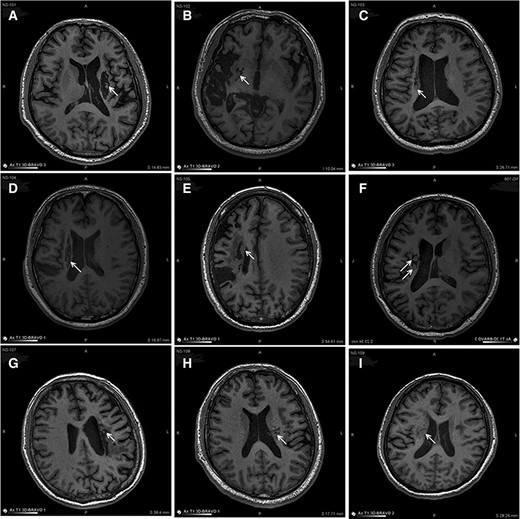

圖3:NSI-566移植后最新隨訪時梗塞部位的MRI。

圖中顯示的是所有9名受試者(#101–109)在NSI-566移植后最新隨訪時的T1MRI圖像。箭頭指示梗塞腔位置。

(A):#101,24個月時,(B)#102,12個月時,(C)#103,14個月時,(D) #104,9個月時,(E)#105,14個月時,(F)#106,24個月時,(G) #107,21個月時,(H) #108,12個月時,(I) #109,14個月時。所有九個病例中梗塞腔內均有新組織生長。